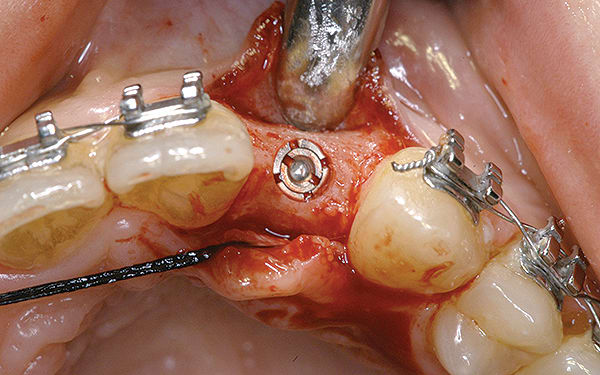

Although prosthodontists are capable of saving many complicated implant cases, the clinical results may still remain esthetically compromised. As opposed to heroic attempts to restore a misaligned implant, there are times when implant removal is a better solution. In the challenging case depicted in Figure 1 through Figure 4, it was determined that the implant, as positioned, could not be adequately restored. Two options were considered: implant removal and replacement with a properly positioned implant and implant replacement or submergence followed by the fabrication of a 3-unit fixed partial denture. The fixed partial denture would take advantage of utilizing tooth No. 8 as an abutment after removing the existing crown but would necessitate involving the virgin tooth No. 10. The surgical/prosthetic team in consultation with the patient elected to remove the implant and place a second implant. The implant was removed and a new implant was placed in the correct vertical and horizontal position using CT-guided surgery.